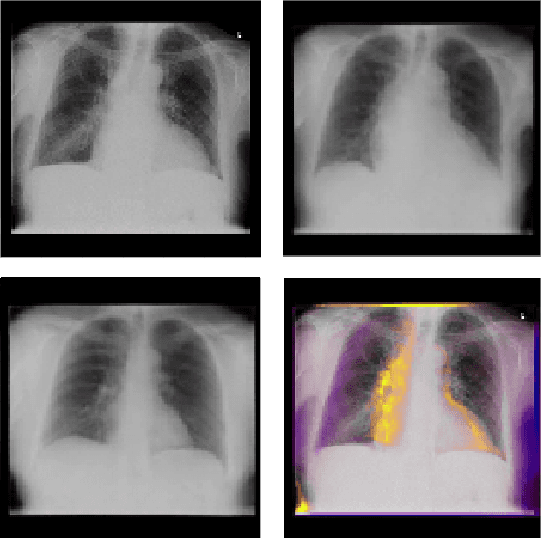

Interpretability and small labelled datasets are key issues in the practical application of deep learning, particularly in areas such as medicine. In this paper, we present a semi-supervised technique that addresses both these issues by leveraging large unlabelled datasets to encode and decode images into a dense latent representation. Using chest radiography as an example, we apply this encoder to other labelled datasets and apply simple models to the latent vectors to learn algorithms to identify heart failure. For each prediction, we generate visual rationales by optimizing a latent representation to minimize the prediction of disease while constrained by a similarity measure in image space. Decoding the resultant latent representation produces an image without apparent disease. The difference between the original decoding and the altered image forms an interpretable visual rationale for the algorithm's prediction on that image. We also apply our method to the MNIST dataset and compare the generated rationales to other techniques described in the literature.